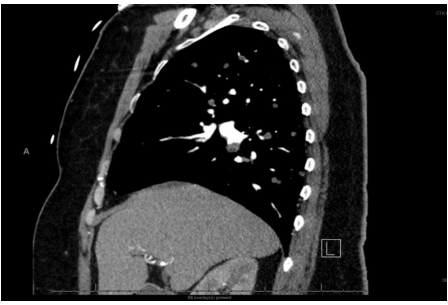

CTA chest (Figure 2) showed numerous pulmonary nodules.

Figure 2: CT chest. Sagittal (Side) view of the Chest showing numerous pulmonary nodules.

The pulmonary nodules are of varying sizes with the largest being about 7mm in size. The nodules are believed to be secondary to metastasis from the primary duodenal mass.